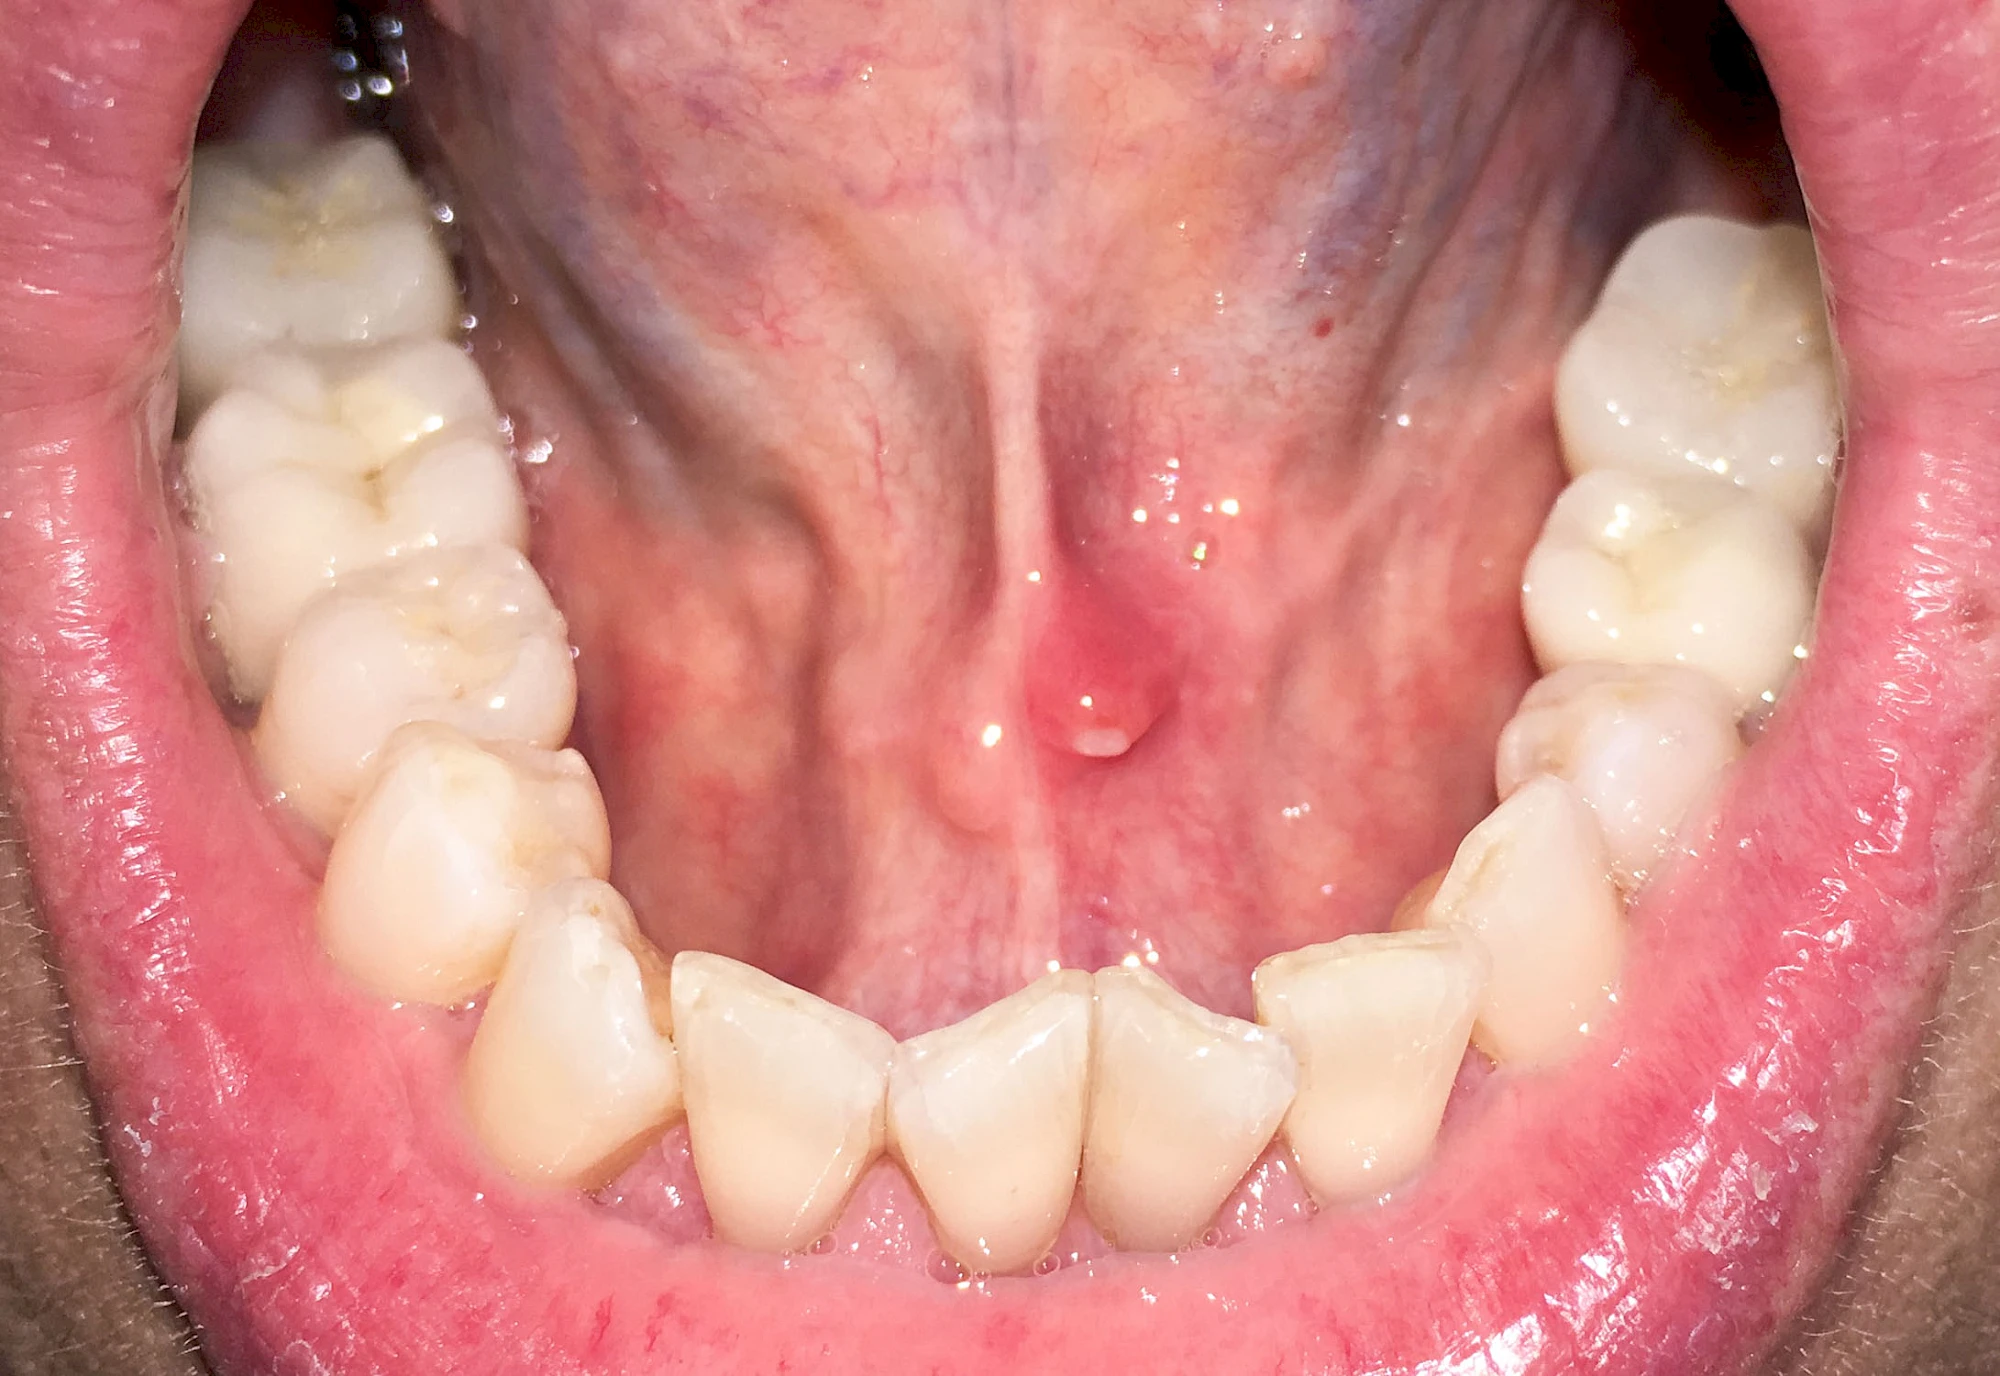

Speicheldrüsenzyste

Eine Speicheldrüsenzyste (Speicheldrüsenretentionszsyte) kann als Schwellung oder Auftreibung meist im Bereich der größeren Ausführungsgängen auffallen, wenn z. B. ein Speichelstein den Speichelfluss behindert. Vor allem bei den Mahlzeiten, wenn der Speichelfluss angeregt wird, nimmt die Auftreibung oder Schwellung schmerzhaft weiter zu. In der Regel ist die Unterkieferspeicheldrüse (Glandula sublinugalis) betroffen. Man spricht dann auch von einer Frosch- bzw. Fröschleingeschwulst (Ranula). Bringt sanftes Massieren der Schwellung bzw. Auftreibung keine Verbesserung, sollte ein Arzt oder Zahnarzt hinzugezogen werden